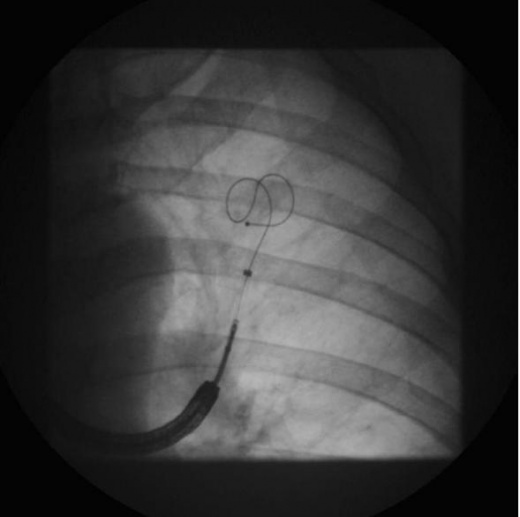

החדרת התקנים מתכתיים בצורת קפיץ המתבצעת באמצעות ברונכוסקופ גמיש מיועדת לחולים עם נפחת הומוגנית או הטרוגנית (PneumRx, Inc., Mountain View, Calif., USA). הפעולה כוללת החדרה לתוך רקמת הריאה של כ-10-20 תיילים מתכתיים באורך 10-20 סנטימטר העשויים ניטינול תחת שיקוף (תמונה מס' 3). ההיגיון הפיזיולוגי מכוון לשיפור של היכולת האלסטית של הריאות הנפחתיות עם הקטנה בכליאת האוויר ושיפור ביכולת התרוקנות הריאות בזמן נשיפה.